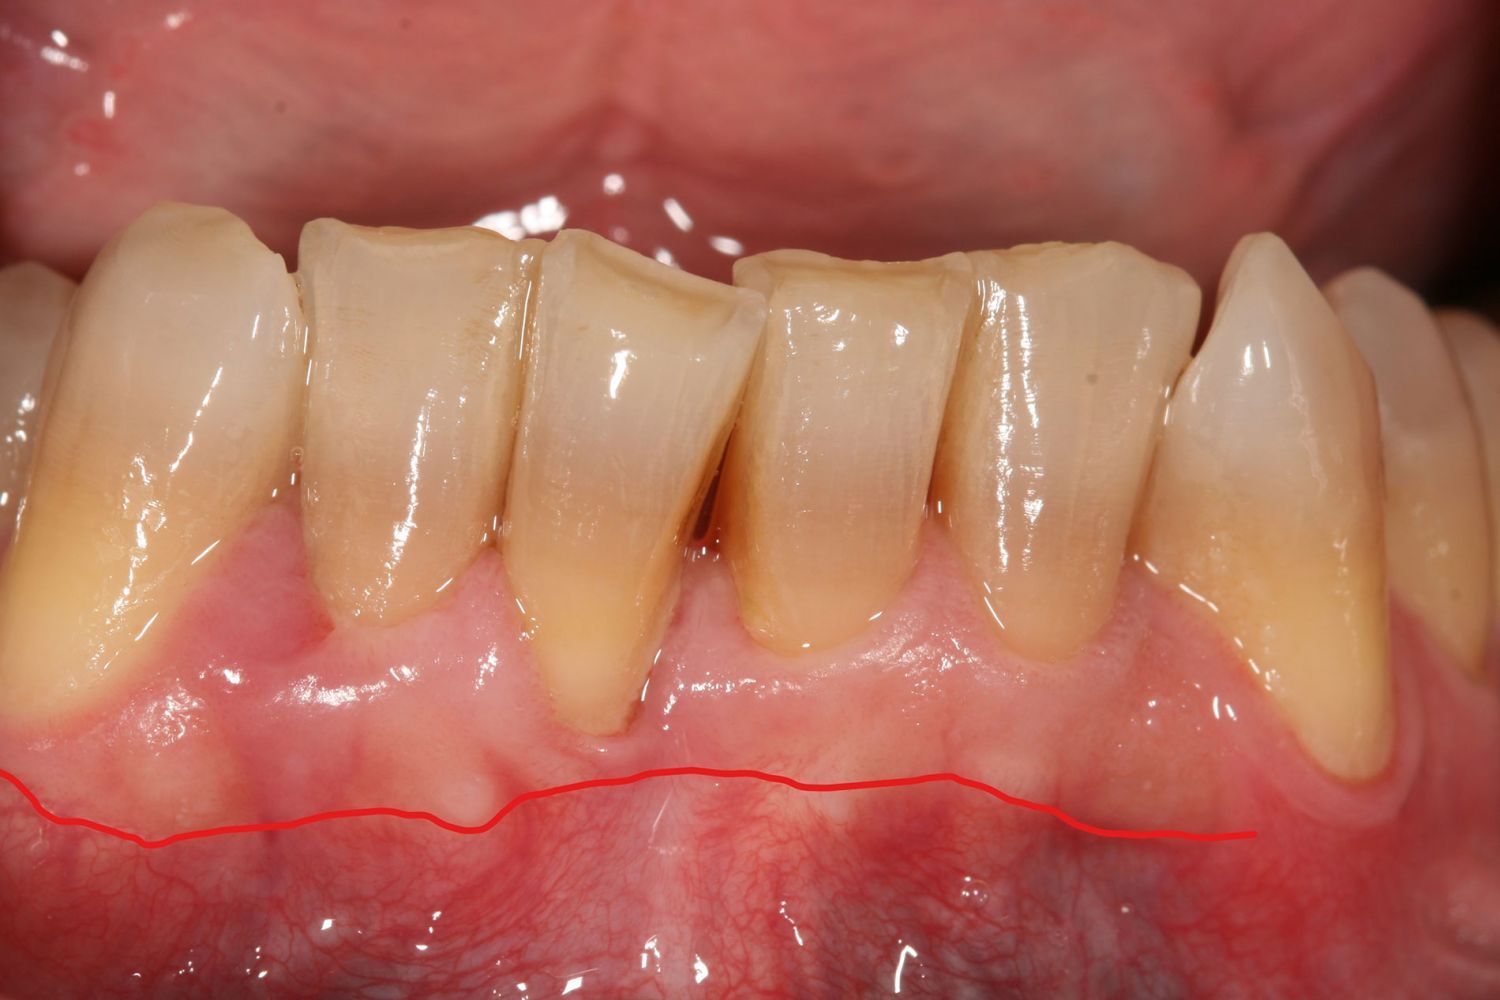

Caso de cirugía periodontal

Cirugía periodontal en un paciente